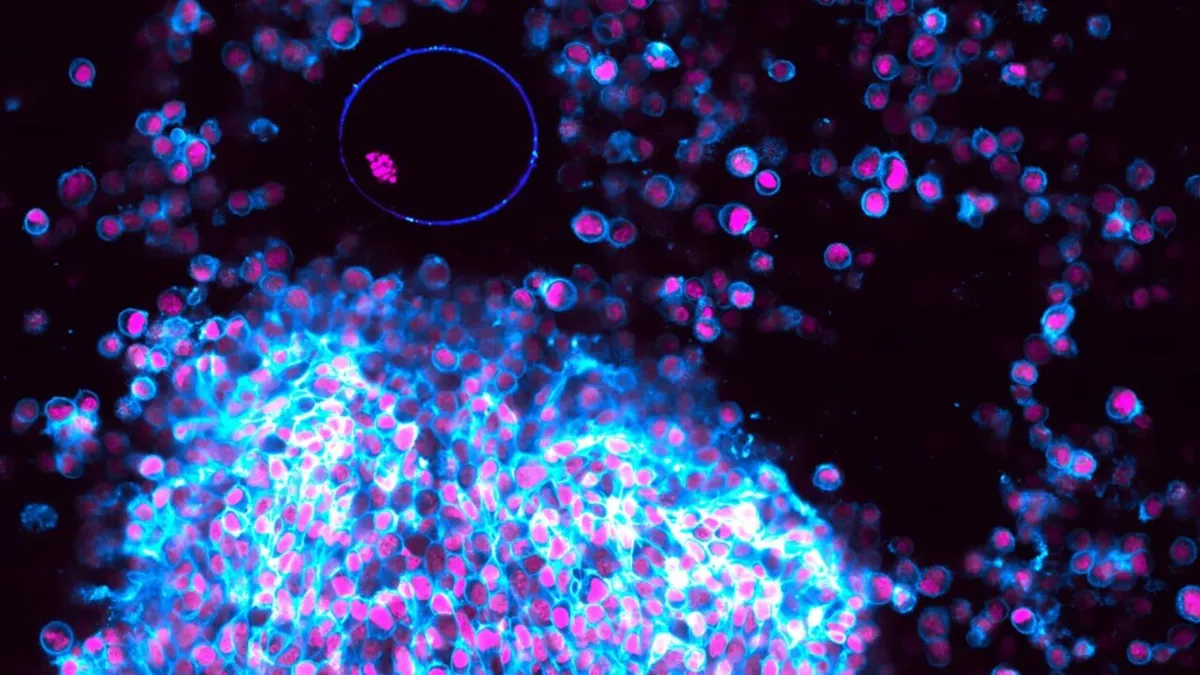

Onderzoekers van het Max Planck-Institut gebruikten een geavanceerde beeldvormingstechniek op follikels van muizen, die buiten het lichaam in een petrischaaltje groeiden. Ze werden gestimuleerd met specifieke hormonen die ovulatie in gang zetten. Met deze methode konden ze het ontstaan en de vrijlating van een eicel stap voor stap filmen, zoals nooit tevoren.

- Fase 1 – Groei van het follikel: Het meest rijpe follikel groeit binnen acht uur bijna twee keer zo groot. Dit komt door de productie van hyaluronzuur, dat zorgt voor instroom van vocht.

- Fase 2 – Samentrekking van de spierlaag: De buitenste spiercellen trekken samen en bereiden de ‘lancering’ van de eicel voor.

- Fase 3 – Vrijlating van de eicel: Uiteindelijk wordt de eicel krachtig naar buiten gestoten en komt in het laboratoriumschaaltje terecht. Precies deze fase is nu schitterend vastgelegd op video.